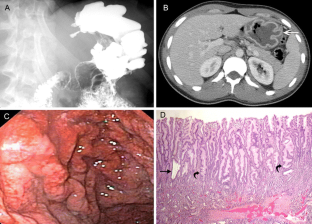

Menetrier's disease egd

Menetrier's disease egd picture This image illustrates Menetrier's disease egd.